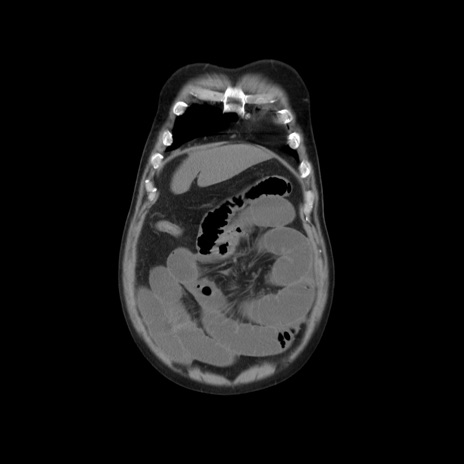

横断像